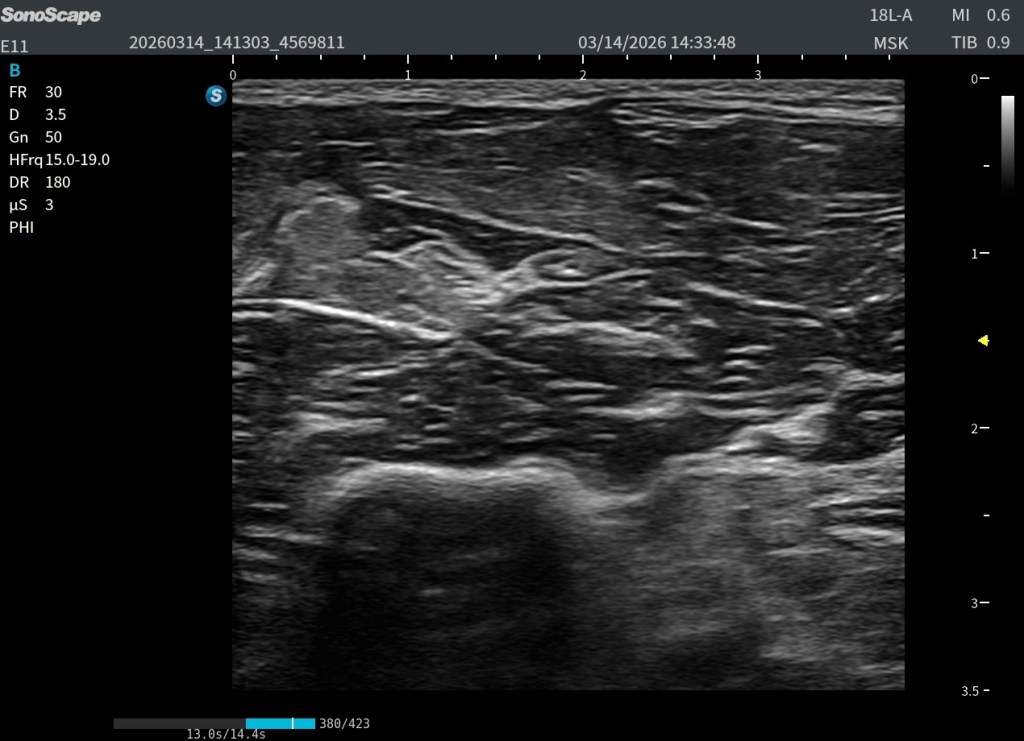

Si utilizamos una frecuencia muy alta, por ejemplo 18 MHz, la resolución en las capas superficiales será excelente. Pero si el músculo es grande o el paciente tiene bastante tejido subcutáneo, el ultrasonido se atenúa mucho antes de llegar a las fibras profundas.

En esa situación llegará menos energía al fondo del músculo y los ecos que regresan serán más débiles. La zona profunda aparecerá más oscura y la relación señal-ruido empeorará.

Si en esa misma exploración bajamos la frecuencia a 10–12 MHz, la penetración del ultrasonido mejora. Los ecos de las fibras musculares profundas regresan con mayor amplitud y la imagen se vuelve más homogénea. Aunque la resolución absoluta sea ligeramente menor, la calidad global de la imagen mejora porque la relación señal-ruido es mejor.